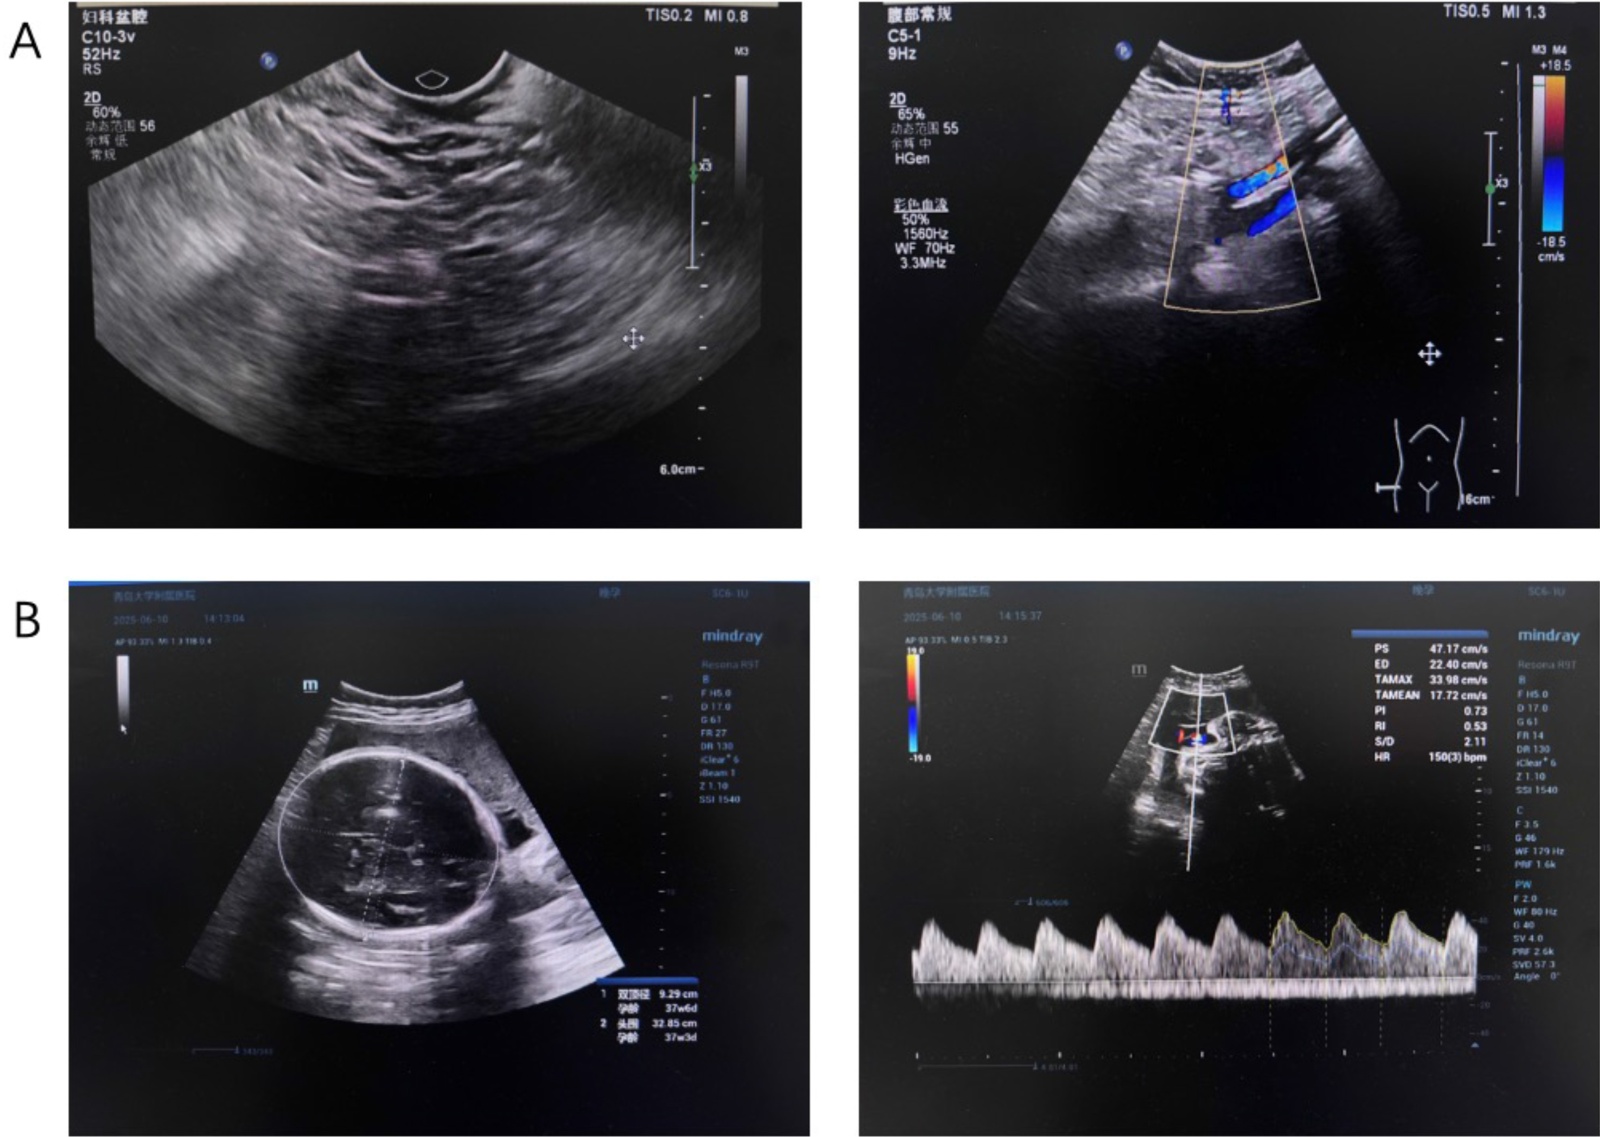

本次妊娠采用激素替代方案进行冻胚移植,使用口服雌二醇(4~6 mg/d)及黄体支持。孕31周4天复查阴道镜发现HPV相关宫颈腺样病变;活检证实为HPV相关腺癌,p16强阳性,Ki-67约80%。盆腔MRI显示宫颈管内16 × 13 mm病灶。实验室检查:CA-125 193 U/mL,CEA 10.2 U/mL,SCC与CA19-9正常。孕35周4天常规产检超声显示胎儿生长符合孕周,无结构异常(图1(A))。

患者术后三个月复查:经阴道超声显示盆腔结构正常,无残余病灶(图1(B))。CA-125降至8.84 U/mL,已恢复正常范围。

Figure 1. Imaging comparison of prenatal fetal ultrasound and postoperative transvaginal ultrasound. (A) Routine prenatal ultrasonography at 35 + 4 weeks of gestation showed fetal growth consistent with gestational age, with no structural abnormalities detected. (B) Postoperative follow-up transvaginal ultrasonography revealed no residual cervical lesions, and no abnormal findings were observed in the pelvic cavity

1. 产前胎儿超声与术后经阴道超声的影像学对比。(A) 孕35 + 4周行产前胎儿超声检查,结果提示胎儿生长发育与孕周相符,未发现明显结构性异常;(B) 术后复查经阴道超声,未见残余宫颈病变,盆腔未发现异常影像学表现